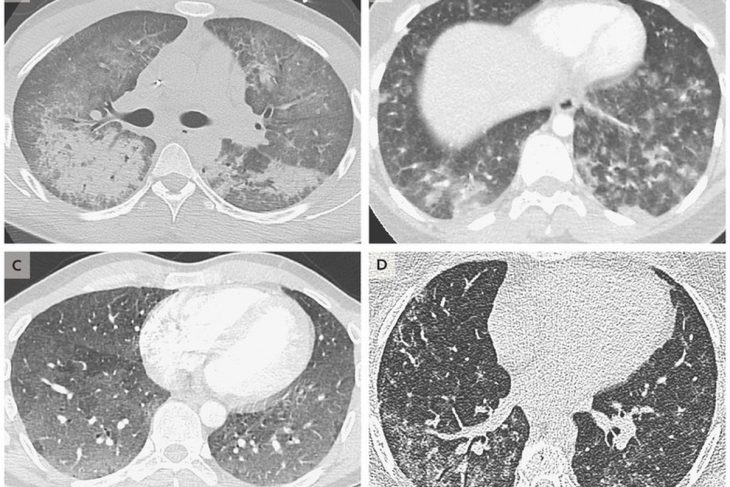

Pakar kesihatan dari Pusat Kawalan Penyakit (CDC) Amerika Syarikat telah pun menemui penyebab penyakit misteri itu. Menurut CDC, asetat vitamin E yang digunakan untuk mencairkan cecair vape mungkin antara puncanya. Ia dibuktikan apabila asetat vitamin E ditemui pada 29 sampel ujian tisu paru-paru pengidap kerosakan paru-paru akibat vape dan produk vape (EVALI).

Dalam sampel yang sama THC (ganja) ditemui pada 82% sampel dan nikotin pula pada 61%. Ini mungkin bukti paling kukuh bahawa asetat vitamin E memberikan kesan buruk pada paru-paru penghisap vape.

Selain itu, asetat vitamin E biasanya hanya digunakan pada cecair vape yang mengandungi THC dan kebanyakan cecair tersebut tidak dijual secara komersial. Tetapi ia tidak menolak kemungkinan bahan tersebut mungin turut digunakan pada cecair vape lain di pasaran.